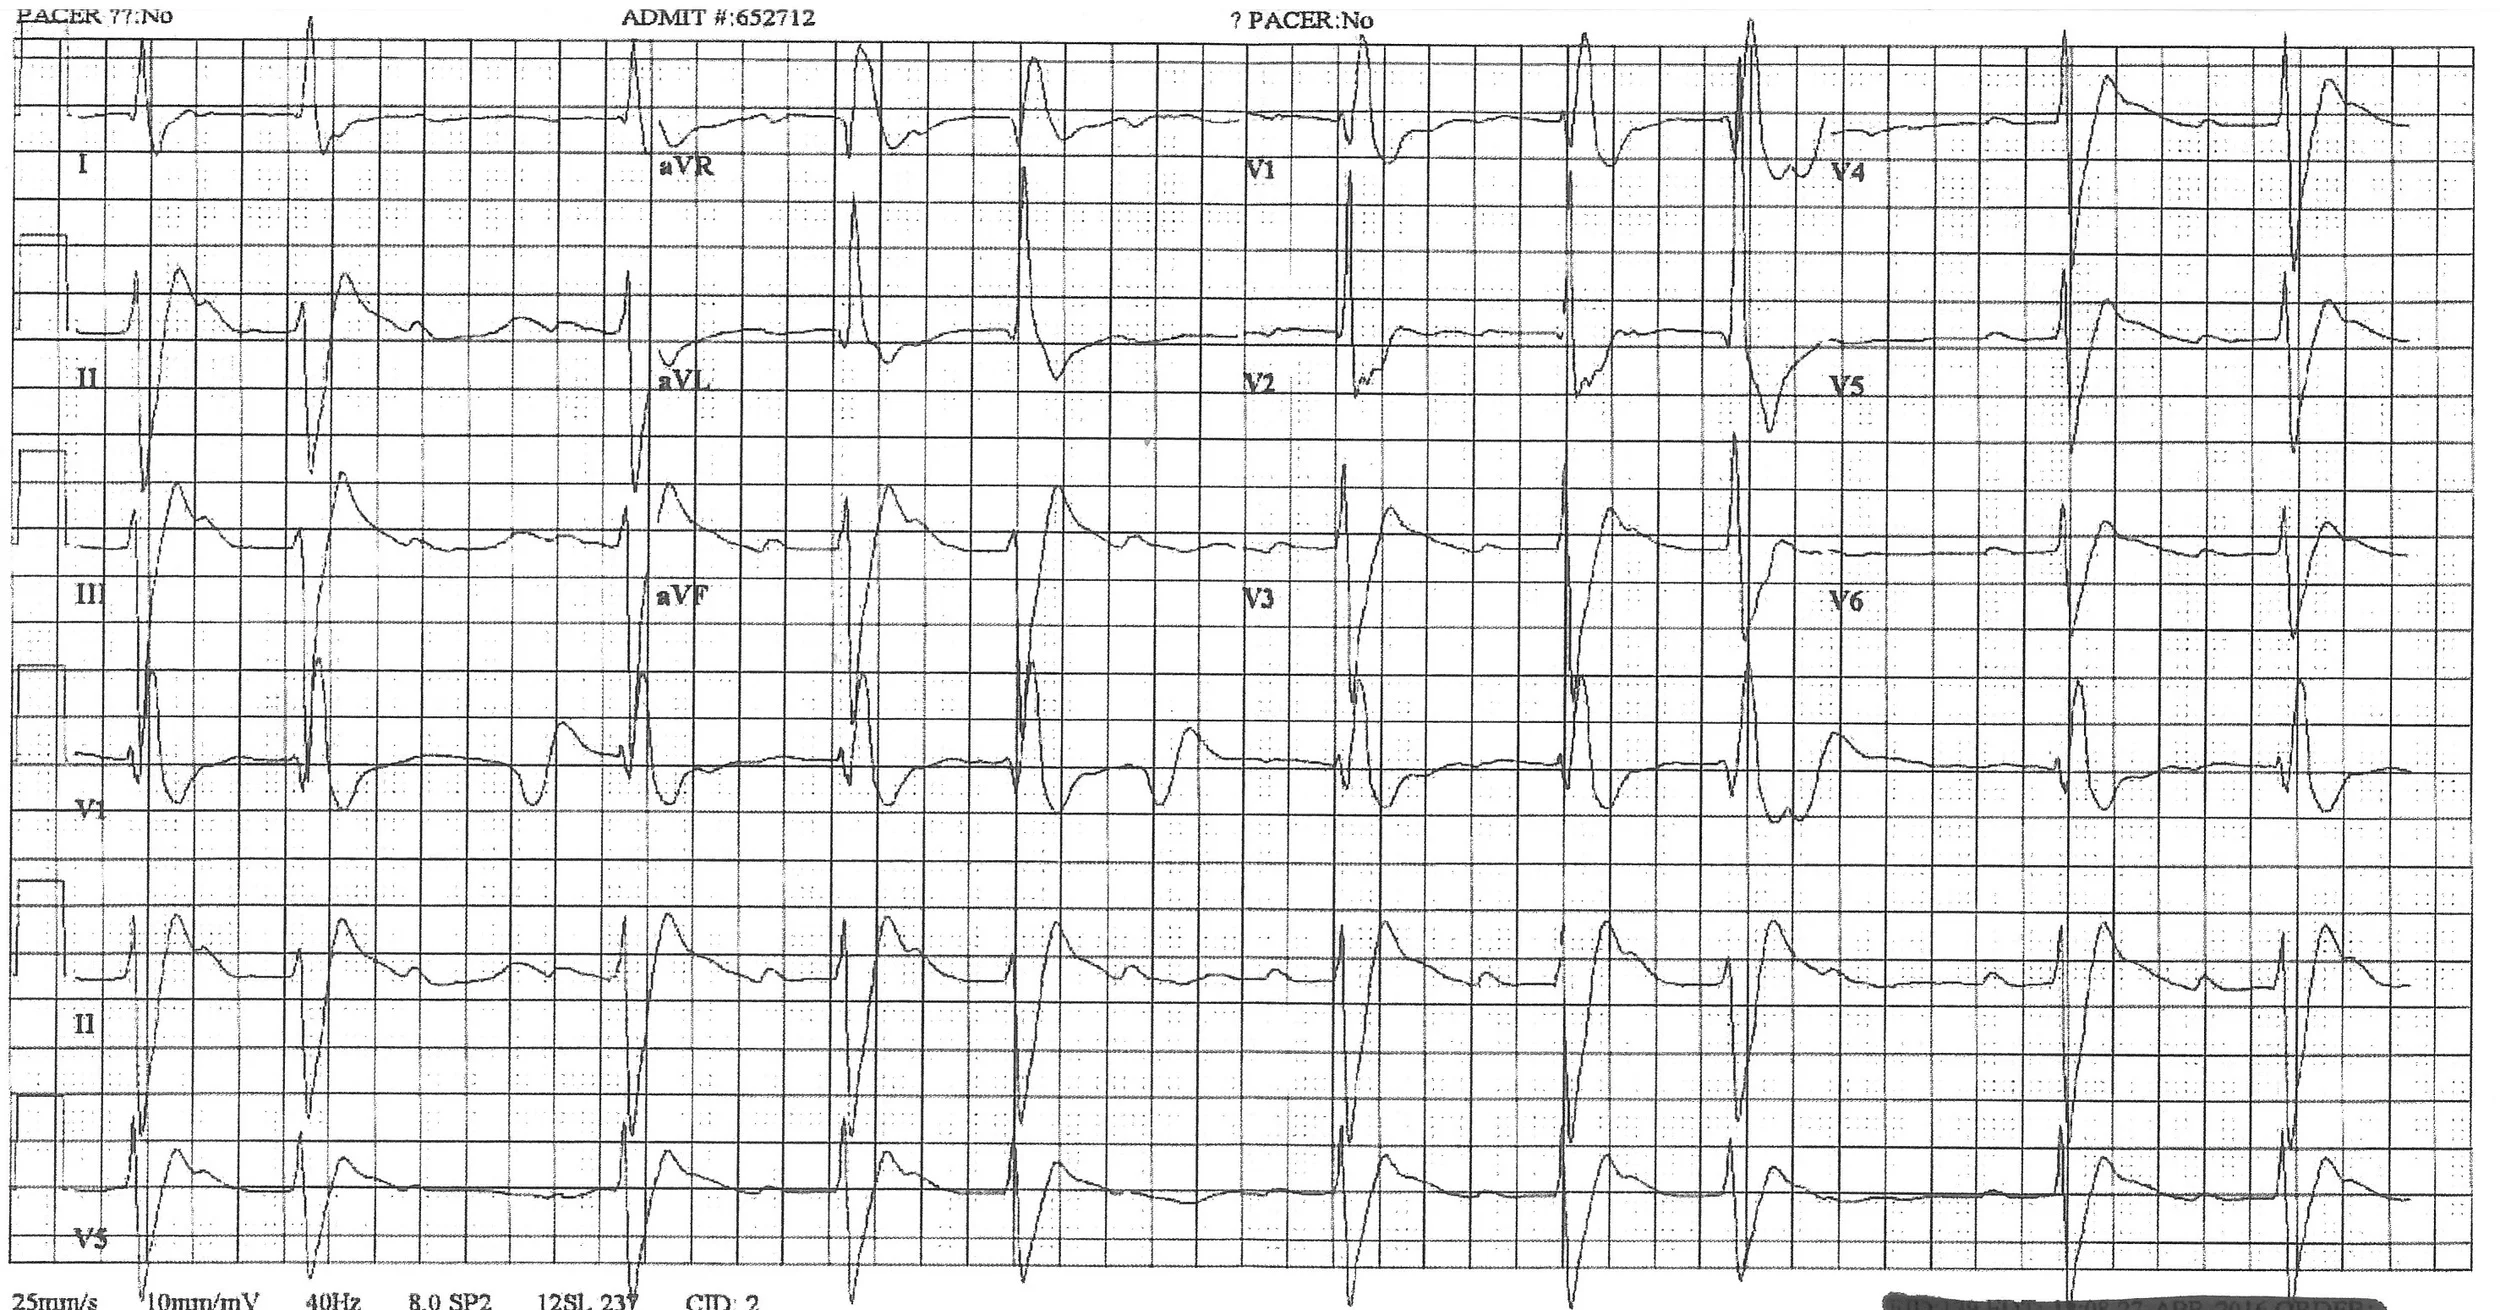

Paramedics bring in a 29 year old male with a history of depression and alcohol abuse for a reported ibuprofen ingestion of unknown quantity as a suicide attempt.  The patient initially was somnolent and admitted to alcohol use, but while being transported suddenly had a generalized tonic-clonic seizure.  Paramedics quickly administer IV diazepam for the resolution of seizure activity, and he is post-ictal on arrival to the ED.  Blood pressure is 98/60 with an irregularly irregular heart rate of 62 on the monitor.  He has no history of seizures or cardiac disease in his records.  His 12-lead EKG shows this:

The EKG machine read this as "Sinus bradycardia with 1st degree A-V block with premature supraventricular complexes, right bundle branch block, left anterior fascicular block, left ventricular hypertrophy with QRS widening and repolarization abnormality."  Great.  But this makes no sense--an ibuprofen overdose doesn't cause EKG changes like this.  SOMETHING is missing in the history!

Most concerning on this EKG are the intraventricular conduction delay (widened QRS) and the prominent R' in aVR, which should raise your suspicion for sodium channel blockade.  It was discovered later by family that there was an empty 100 tablet bottle of 50 mg diphenhydramine tablets at the house that was full just a few days prior.